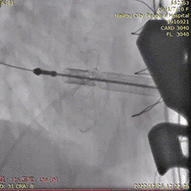

释放J-Valve瓣膜后造影可见瓣膜形态良好